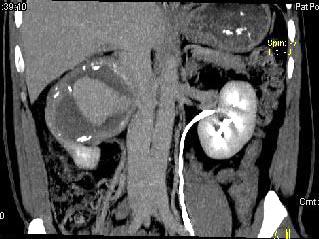

问题 男,48岁,反复腰酸、腰痛伴镜下血尿2年,加重3天,无尿频、尿急、尿痛,无低热、盗汗、咳嗽,右肾区叩击痛,CT检查如图所示,应诊断为 ( )

选项 A、右肾错构瘤 B、右肾盂癌 C、右肾癌 D、急性右肾内血肿 E、右肾动脉瘤

答案 E